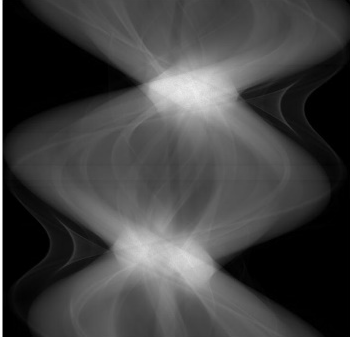

Low-Dose Computed Tomography (LDCT) technique, which reduces the radiation harm to human bodies, is now attracting increasing interest in the medical imaging field. As the image quality is degraded by low dose radiation, LDCT exams require specialized reconstruction methods or denoising algorithms. However, most of the recent effective methods overlook the inner-structure of the original projection data (sinogram) which limits their denoising ability. The inner-structure of the sinogram represents special characteristics of the data in the sinogram domain. By maintaining this structure while denoising, the noise can be obviously restrained. Therefore, we propose an LDCT denoising network namely Sinogram Inner-Structure Transformer (SIST) to reduce the noise by utilizing the inner-structure in the sinogram domain. Specifically, we study the CT imaging mechanism and statistical characteristics of sinogram to design the sinogram inner-structure loss including the global and local inner-structure for restoring high-quality CT images. Besides, we propose a sinogram transformer module to better extract sinogram features. The transformer architecture using a self-attention mechanism can exploit interrelations between projections of different view angles, which achieves an outstanding performance in sinogram denoising. Furthermore, in order to improve the performance in the image domain, we propose the image reconstruction module to complementarily denoise both in the sinogram and image domain.

翻译:降低对人体的辐射伤害的低剂量成像技术(LDCT)正在引起人们对医疗成像领域的兴趣。由于低剂量辐射导致图像质量下降,LDCT考试需要专门的重建方法或解密算法。然而,最近大多数有效方法忽略了原始投影数据的内部结构(Sintmag),这种数据限制了它们的分泌能力。罪状的内结构是罪状图领域数据的特殊特征。通过在解密的同时保持这一结构,噪音可以明显地受到限制。因此,我们建议使用Singraph Inner-Strockre变异器(SIST)来降低图像质量网络的噪音,以便利用罪状领域的内部结构来减少噪音。具体地说,我们研究染色学的CT成像机制和统计特征来设计罪状内结构损失,包括恢复高质量CT图像的全球和地方内部结构。此外,我们提议使用一种罪状变形模型模块来更好地提取罪状特征。因此,我们提议使用一种自我观察的变形结构,在罪状模型中可以利用一种杰出的域域图的性变图,从而改进了不同图像的成图。